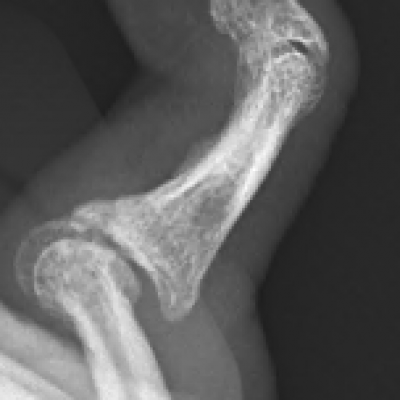

Arthritis can affect any joint in the body. The most common types of arthritis include osteoarthritis, rheumatoid arthritis and post-traumatic arthritis. Osteoarthritis is a degenerative joint disease where the smooth cartilage covering the bone ends, wear out, causing pain, swelling and stiffness and in the hand commonly affects the PIP joint, DIP joint and base of thumb (CMC joint). It commonly occurs in older people.

Common symptoms cause pain, and stiffness in the small joints of the hand. The knuckles can become swollen or show bumps and bony nodules called Heberden’s or Bouchard’s nodes in the fingers. Base of thumb arthritis can sometimes lead to the thumb being drawn into the palm and loss of a wide hand span. People often complain of difficulty opening jars and taps. X-Rays are often the most simple and effective way of showing arthritis.